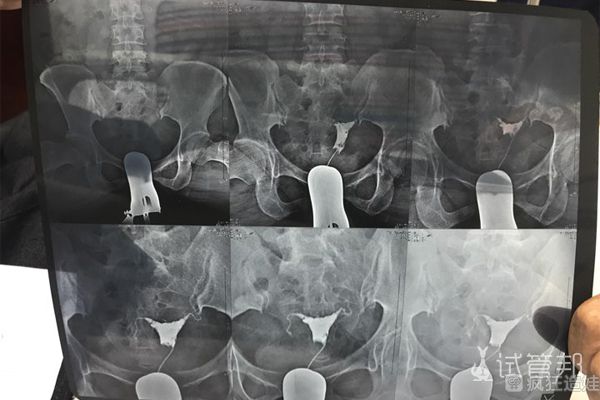

2021年试孕1年,没怀,月经正常排卵正常,来月经也不肚子疼,朋友说不行吃点中药调理一下,就去看了中医;查了激素六项、B超、监测排卵都正常后,大夫建议我做输卵管造影,..